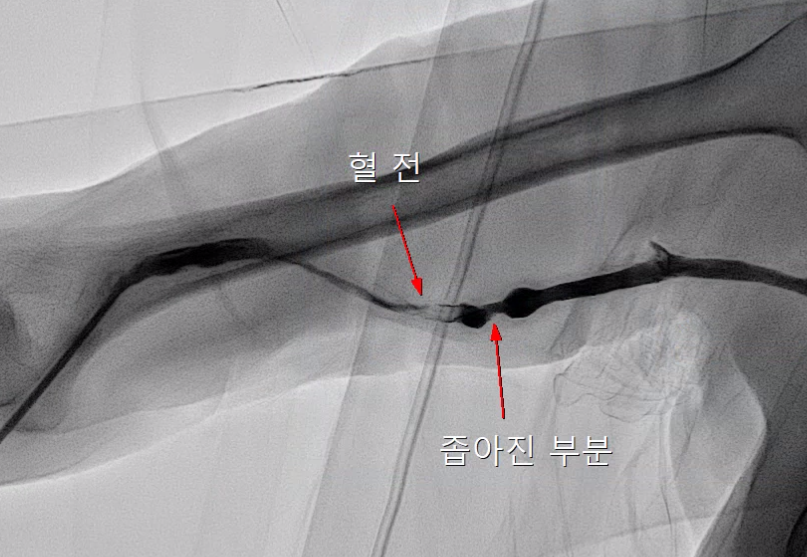

투석혈관 기능부전은 여러가지 이유로 투석혈관이 좁아지거나 막히는 현상을 말합니다.

동맥과 정맥의 압력 차이 때문에도 혈관이 좁아지고, 수술 중 (굉장히 조심하시지만) 혈관에 자극이 가서 연결 부위가 좁아지는 경우도 있고, 연결 했음에도 투석 혈관이 미성숙해서 넓혀지지 않는 경우도 있습니다.

경피적 혈관성형술이란 피부를 미세 절개한 뒤, 직접 혈관으로 접근해서 좁아진 혈관을 확장해주는 시술입니다.